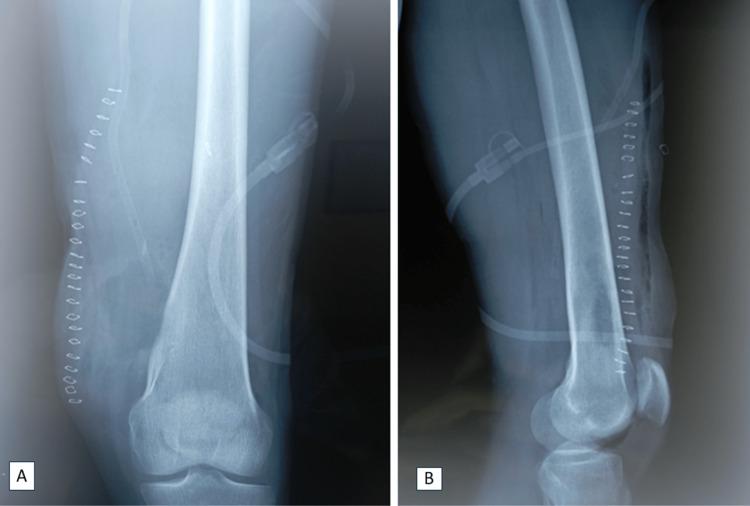

Osteochondromas are benign bone tumors that usually occur between the ages of 10 and 30, with no marked gender preference. These lesions result from the separation of the epiphyseal growth plate and are categorized as growth plate development abnormalities rather than true neoplasms. It is important to note that long-term solitary osteochondromas can evolve into osteosarcomas, with chondrosarcoma being the most common among them. However, the risk of recurrence is considerably reduced if the tumor is completely resected from its original site, with no residual perichondrium or cartilage cap left in place. In this context, a 29-year-old man with osteochondroma in the distal femur was successfully treated with complete resection, showing a favorable evolution.

骨软骨瘤是一种良性骨肿瘤,通常发生在10岁至30岁之间,无明显性别差异。这些病变是由于骨骺生长板分离所致,被归类为生长板发育异常而非真正的肿瘤。需要注意的是,长期存在的孤立性骨软骨瘤可演变为骨肉瘤,其中软骨肉瘤最为常见。然而,如果肿瘤从其原发部位完全切除,且不残留软骨膜或软骨帽,则复发风险会大大降低。在此背景下,一名29岁患有股骨远端骨软骨瘤的男性患者通过完全切除成功治愈,病情进展良好。